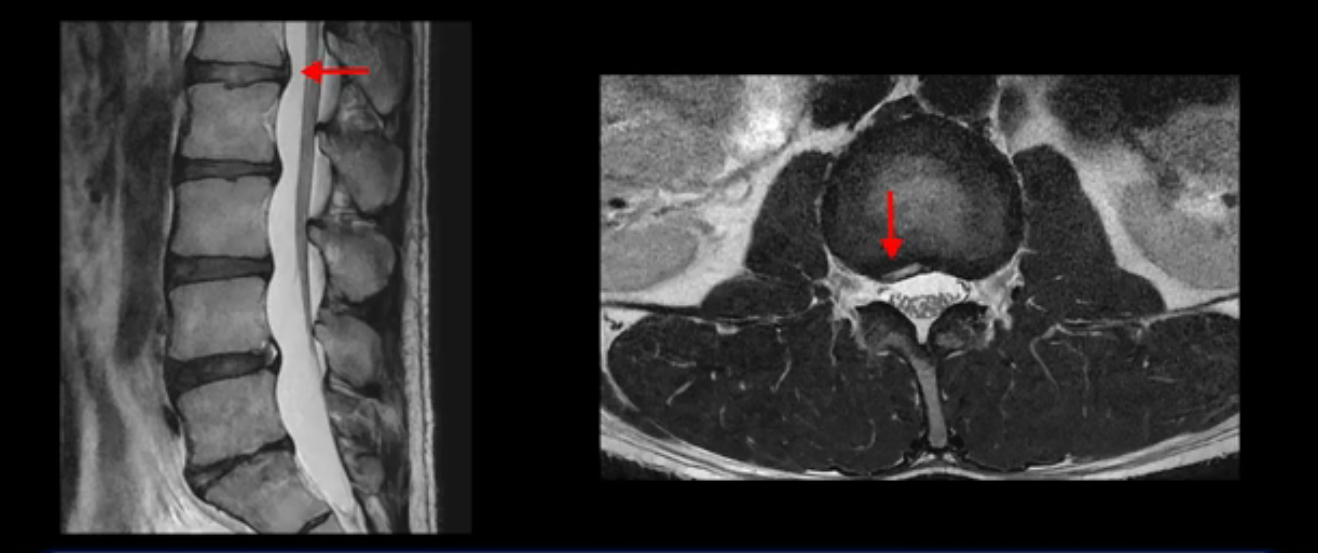

우선 이분 MRI를 보면 허리 모든 마디의 디스크가 퇴행되어 있고

여러 마디의 디스크가 조금씩 밀려나와 보이고, 디스크 섬유륜도 찢어져 보이는 마디도 보입니다.

그런데 이분의 증상과 MRI가 전혀 일치하지 않는데, 왜 그런지 지금부터 자세히 설명드립니다. 이분 증상은 앉으면 엉치와 허리가 심하게 아파 10분 이상 앉는 게 어렵고 양쪽 발가락이 앉아있을 때나 누워있을 때 다 저립니다. 걸을 때도 아파서 10분 걷기도 어렵습니다. MRI를 마디마디 살펴보면 1번 2번은 오른쪽으로 살짝 밀려나온 디스크가 있지만 전혀 심하지 않고, 뒤에 또 설명하겠지만 최근에 밀려나온 급성 디스크가 아니고 오래된 디스크로 판단됩니다.